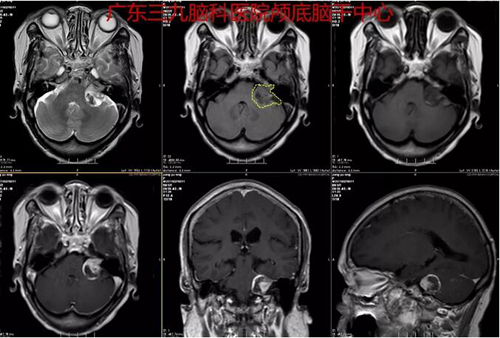

图2:术前MR示左侧桥小脑角区示一团块状长T1长、短混杂T2异常信号影,大小约26mm×23mm×22mm,增强后病灶呈不均匀明显强化,其内示斑片状无强化区。双侧大脑半球皮层下白质内、双侧放射冠及半卵圆中心示散在斑点状等T1长T2异常信号影,FLAIR序列呈高信号。脑室系统轻度扩张。